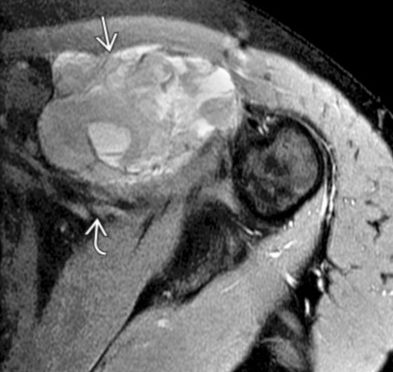

Synovial Sarcoma

• Misnomer as does not actually arise from synovium or in the joint but typically adjacent to joint

• Strong predilection for the extremities

• Relatively young 15-40 yo

• Slow growing and does not have to be painful

• Calcifications about 1/3 of the time

• Not required but commonly located next to a neurovascular bundle (popliteal space, anterior shoulder for example)

• Triple sign

• 3 different densities

• Looks like teratoma in the soft tissue, sometimes, other times just looks like a fucked up mass

• Split fat sign

• Very thin line of fat along periphery of mass, very subtle

• Heterogenous on MR with internal necrosis